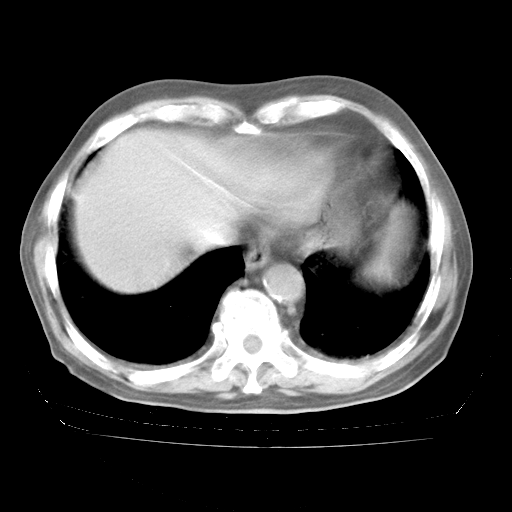

4月28日肺部CT——再次出现类似去年5月9日——透光度降低,“间质性”改变。

4月28日肺部CT

个人阅读4.14日肺部CT平扫:纵隔窗无异常,但肺窗示:双下肺内、后基底段有片絮状侵润影,部位以后基底段为著,以间质改变为主,呈急性肺泡炎征像,和首次住院影像学有相似之处。仅是个人读片,明日请相关专家再读片哈。其它建议同上。

今请临免主任会诊后认为:4月14日胸部CT已有双下肺间质性改变。患者病情复发多系激素减量过快不正规所致。目前甲强龙80mg/日,一周后酌情开始减量,不易过快。环磷酰胺若已停用,暂不使用。他同意目前抗菌药物使用,但应考虑是否加用B-内酰胺类抗菌药物(中性细胞明显增高);2、结核复发目前依据不足;3、若免疫全套各项指标正常,考虑多系特发性肺间质炎可能大。4、加强支持,并注意保护胃黏膜。